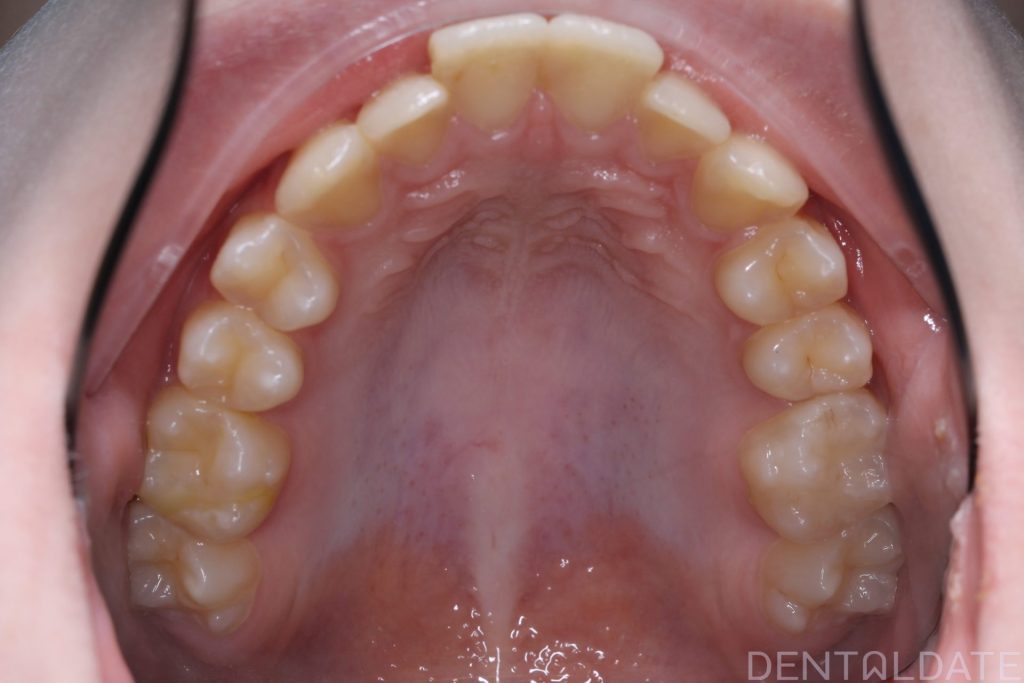

A splint was made in the therapeutic (correct) jaw position, ensuring there was no risk to the joint.